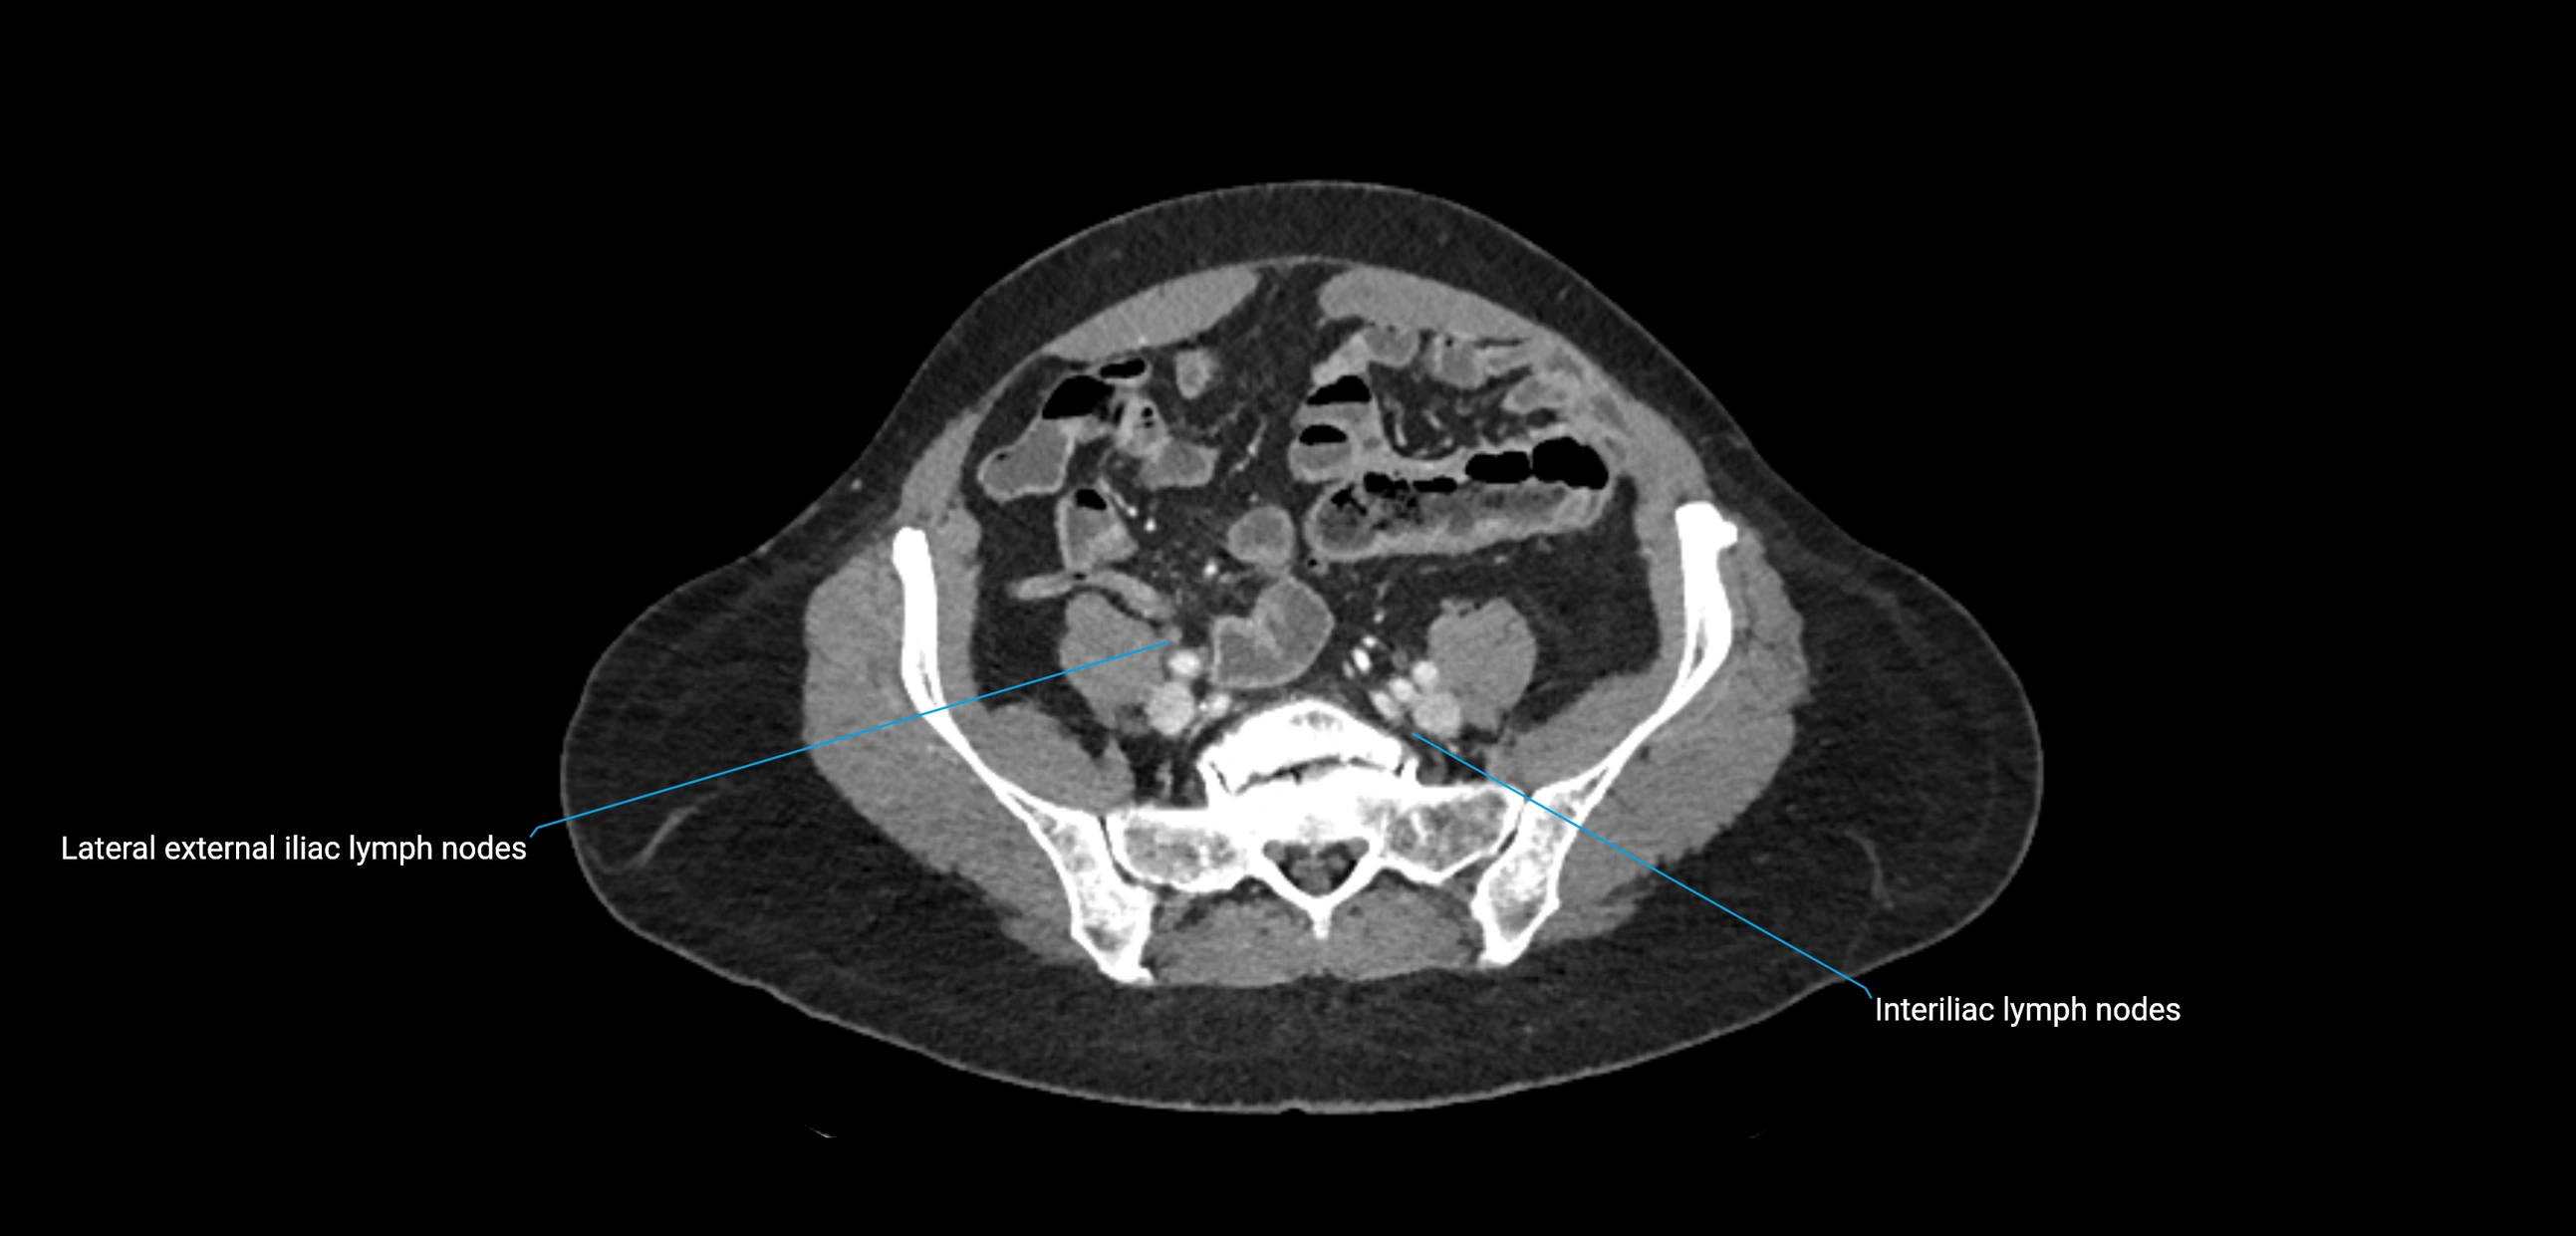

MRI images

image